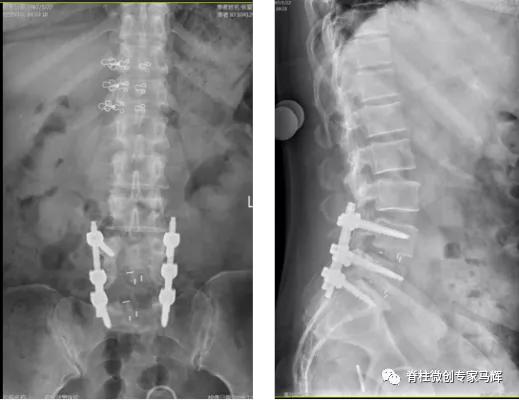

2018年腰椎术后

术后